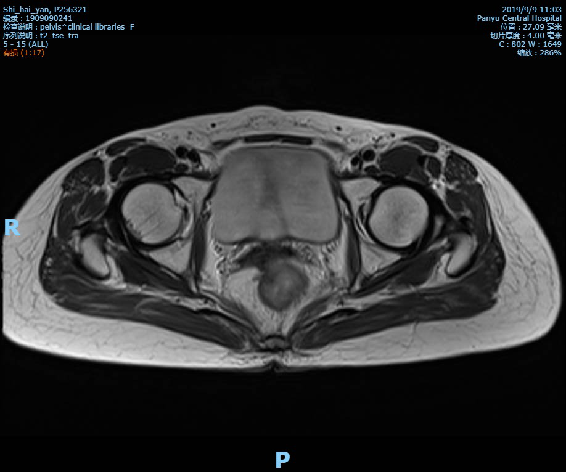

2019-10-09复查盆腔MR示直肠全段管壁不均匀增厚,以中段较明显,最厚处约11mm,较前相仿,仍考虑直肠癌累及浆膜面,较前略有好转,不除外直肠前筋膜受累;胸腹CT未见转移征象。

术前影像学检查: